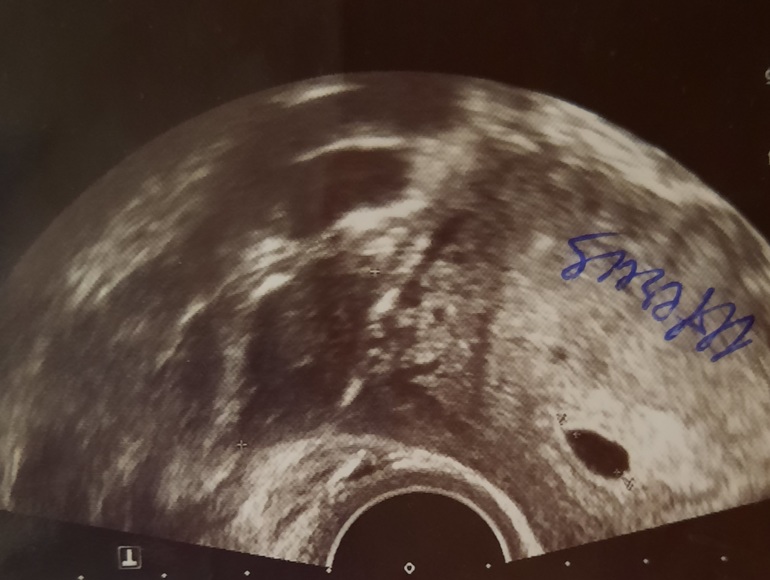

Пол малышаЕсть тут эксперты по методу Рамзи?)

Узи трансвагинальное, 5+5 срок.

Хорион - белая область то ли справа, то ли слева? 🤔

Суть метода в расположении хориона, а не эмбриона)) У Вас по правой стороне, насколько вижу. Значит, мальчик, согласно этому методу.

На каких нужных неделях? Метод работает на 6-7 неделе, у меня 6 неделя)

Простите что лезу но Вы эксперт.я уверена.гляньте что там у меня? Я вообще ничего не соображаю.узи 5 и 6д

О, я совсем не эксперт)))) И вижу только на очевидных фото. У вас очень маленькое, простите 😔 возможно девочка